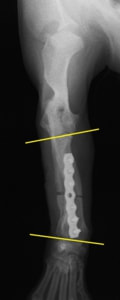

症例:柴犬 3歳

左後肢の完全挙上を主訴に来院されました。触診にて近位足根関節の過伸展を、レントゲン検査にて左足根関節周囲の軟部組織の腫脹、ストレス撮影によって距骨・踵骨と第4足根骨・中心足根骨間の脱臼および過伸展を認めました。

術中において、浅趾屈筋腱を剥離、内方へ牽引し、直接踵骨から第4足根骨までピンを挿入し(あらかじめ細いピンで下穴をあけておくとよい)、テンションバンドワイヤー法を併用し、関節軟骨の掻爬と海綿骨移植を実施しました。

術後レントゲン画像上に癒合が認められるまで約2ヵ月間は、運動を制限する必要があります。

術前正面像左関節の腫れ

左足根関節の軟部組織が腫脹しています。

術前正面像